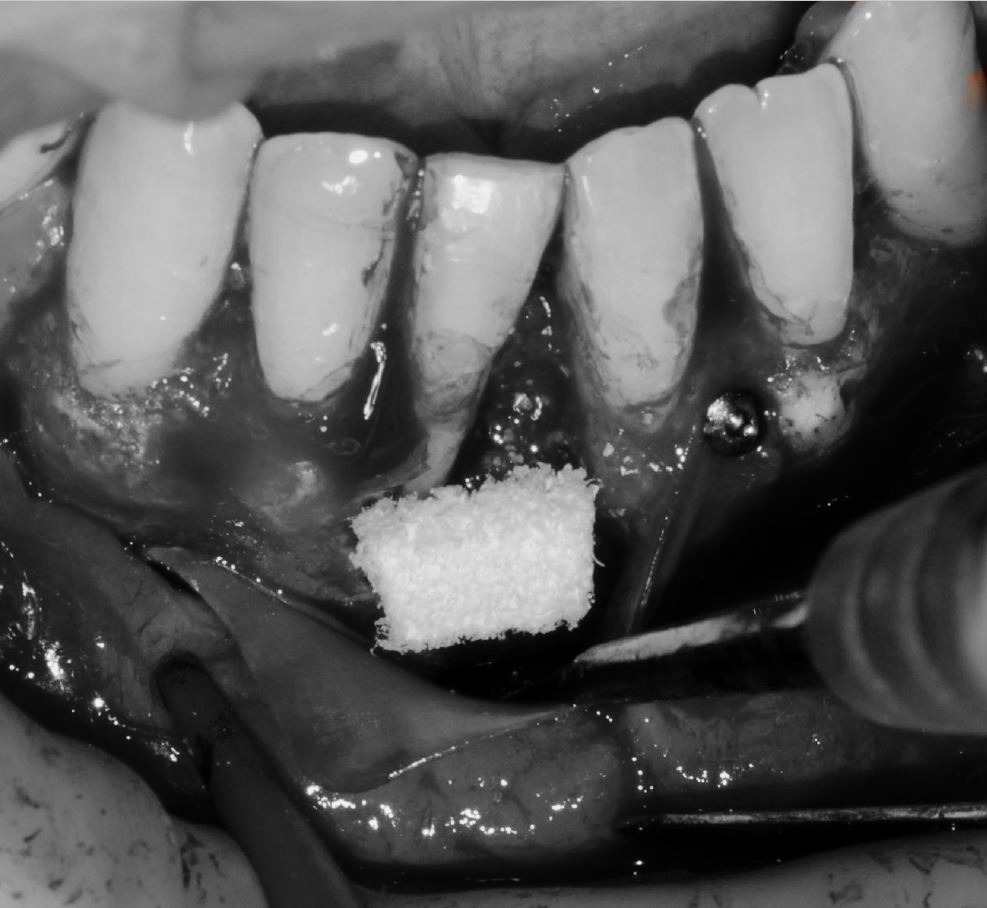

Objetivos periodontales: Regeneración osea guiada con bioss collagen y emdogain.

- Eliminar tejido necrótico. Regeneración periodontal cemento, ligamento y hueso

- Mejora de la estabilidad y soporte óseo

- Estabilidad periodontal y reducción de la movilidad

Profilaxis mediante airflow y descontaminación periodontal. Más ferulización periodontal

R.A.R. Profundo suave intraquirúrgico

Aplicación protocolo emdogain

Regeneración ósea guiada con membrana de colageno creos de Nobel Biocare y relleno óseo mediante BIOSS Collagene de INIBSA, con elementos de fijación a la membrana para R.O.G.

Fotografías del proceso: